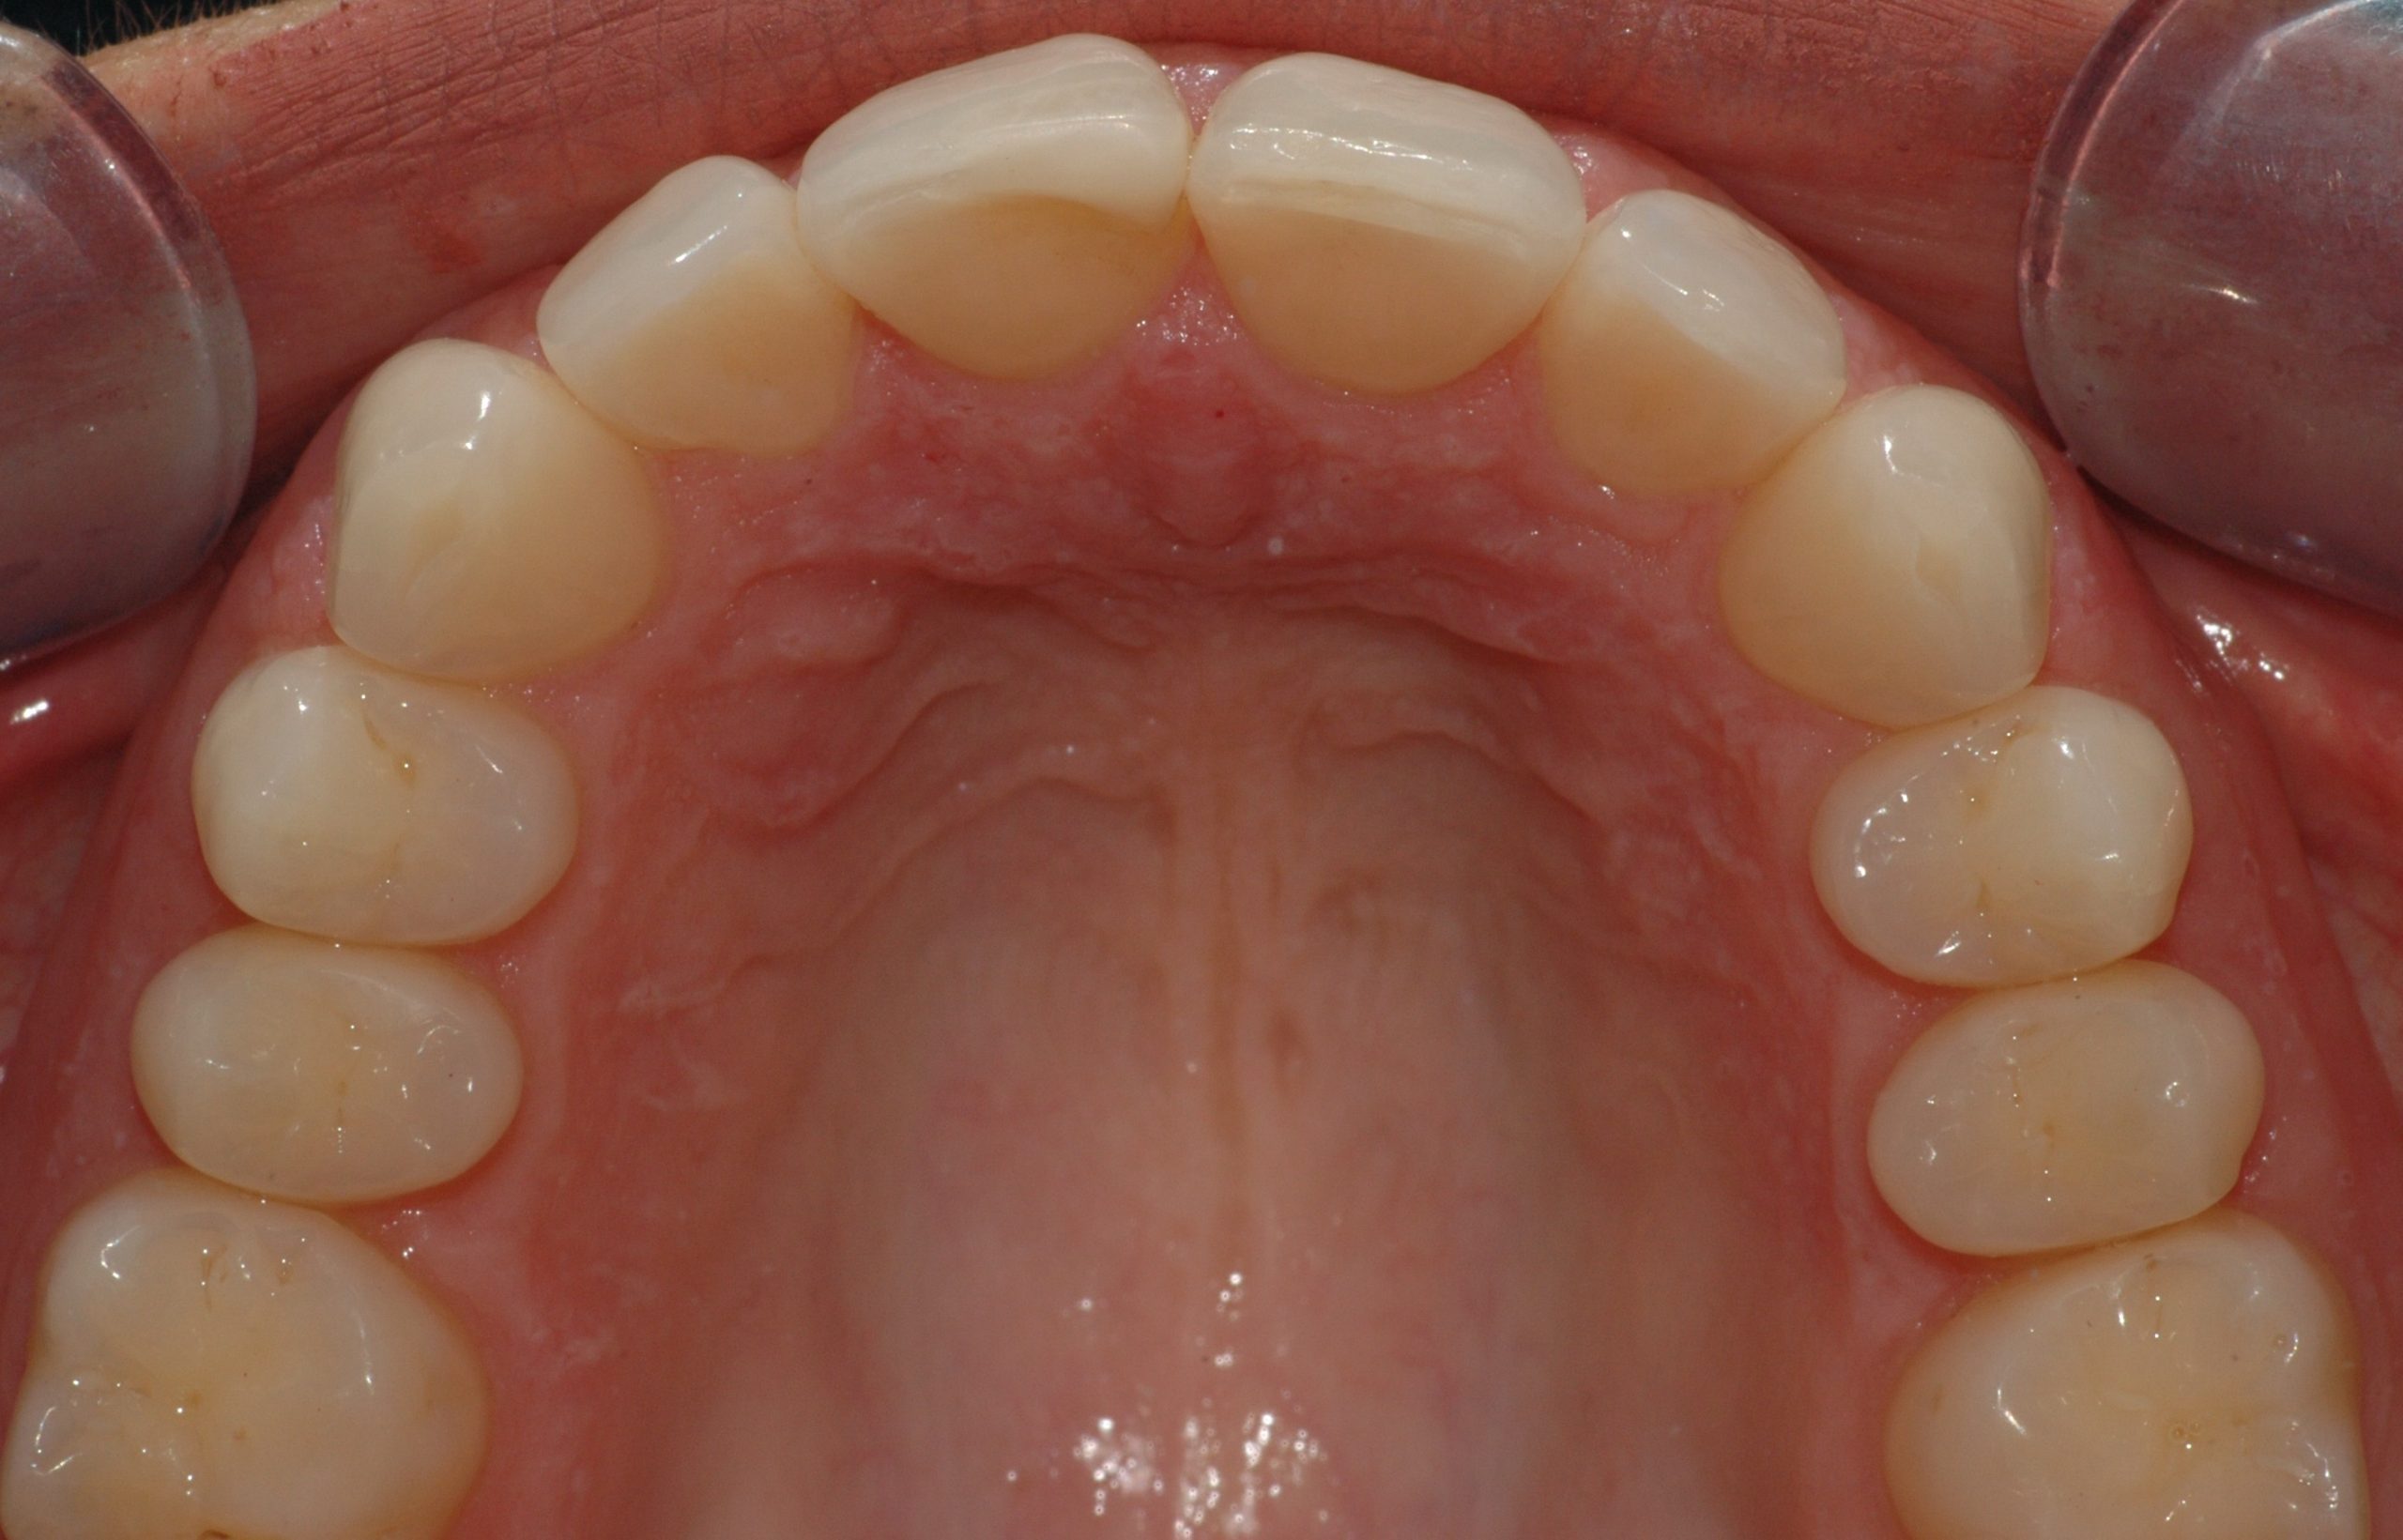

Caso clinico

La paziente presenta malposizione degli incisivi antero-superiori, in particolare un forte sventagliamento degli incisivi laterali. In seguito a trattamento con allineatori trasparenti, durato 9 mesi, si è ottenuto un allineamento pienamente soddisfacente.

PRIMA

DOPO